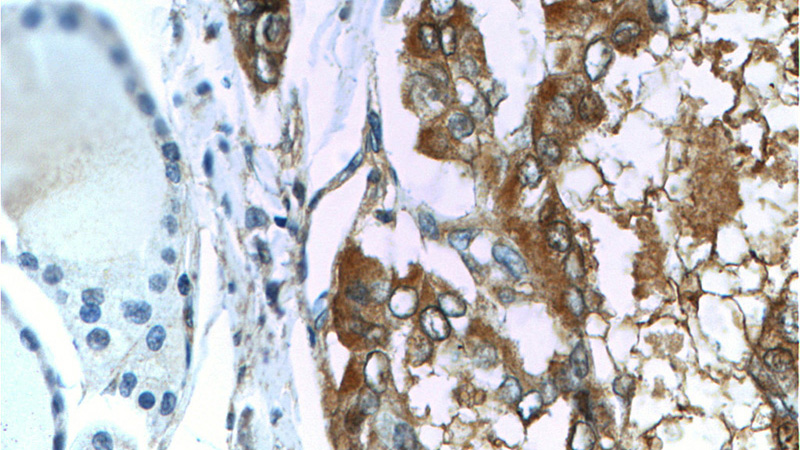

Galectin-3 Mouse Monoclonal antibody. Positive WB detected in Hela cells. Positive IHC detected in human thyroid cancer tissue, human colon tissue. Positive IF detected in MCF-7 cells. Observed molecular weight by Western-blot: 31 kDa

Immunohistochemistry of paraffin-embedded human thyroid cancer tissue slide using Catalog No:107286(Galectin 3 Antibody) at dilution of 1:100 (under 40x lens)